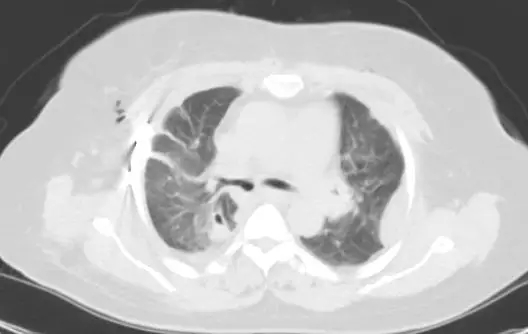

▲ 术前影像资料

经紧急术前准备后,于凌晨3:00在手术室胡强夫主任团队精心麻醉下,由高兴才主任、邢志嵩副主任医师团队行“右主支气管成形术+隆突重建术+右侧多发肋骨骨折切开复位内固定术”,术中探查发现:右主支气管于隆突处完全断裂分离。在高兴才主任医师团队的精细操作下,历经2小时顺利完成手术。

▲ 术后影像资料